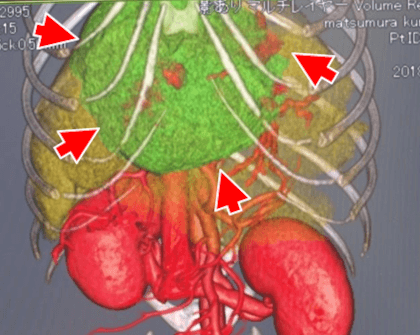

TAE後経過 ②

TAE後66日目 残存腫瘤の摘出手術

― 手術時のCT検査ではPR  ― 組織検査結果は胆管細胞腺腫

第225病日現在、再発なく全身状態良好

外科手術時(TAE後66日目)

TAE前

【考察】

腹腔内出血を伴った肝腫瘤の猫に対し、緊急止血を目的にTAEを実施した。

塞栓術に要した時間は80分であり、手術と比べ比較的短時間で施行可能であった。

残存腫瘤の摘出も安定した状態で実施可能であった。

猫の腹腔内出血は生存退院率が1割強と予後が悪く、手術リスクも高い。

非外傷性の腹腔内出血に対し、止血を目的とした血管内治療は予後改善のために有効となる可能性がある。